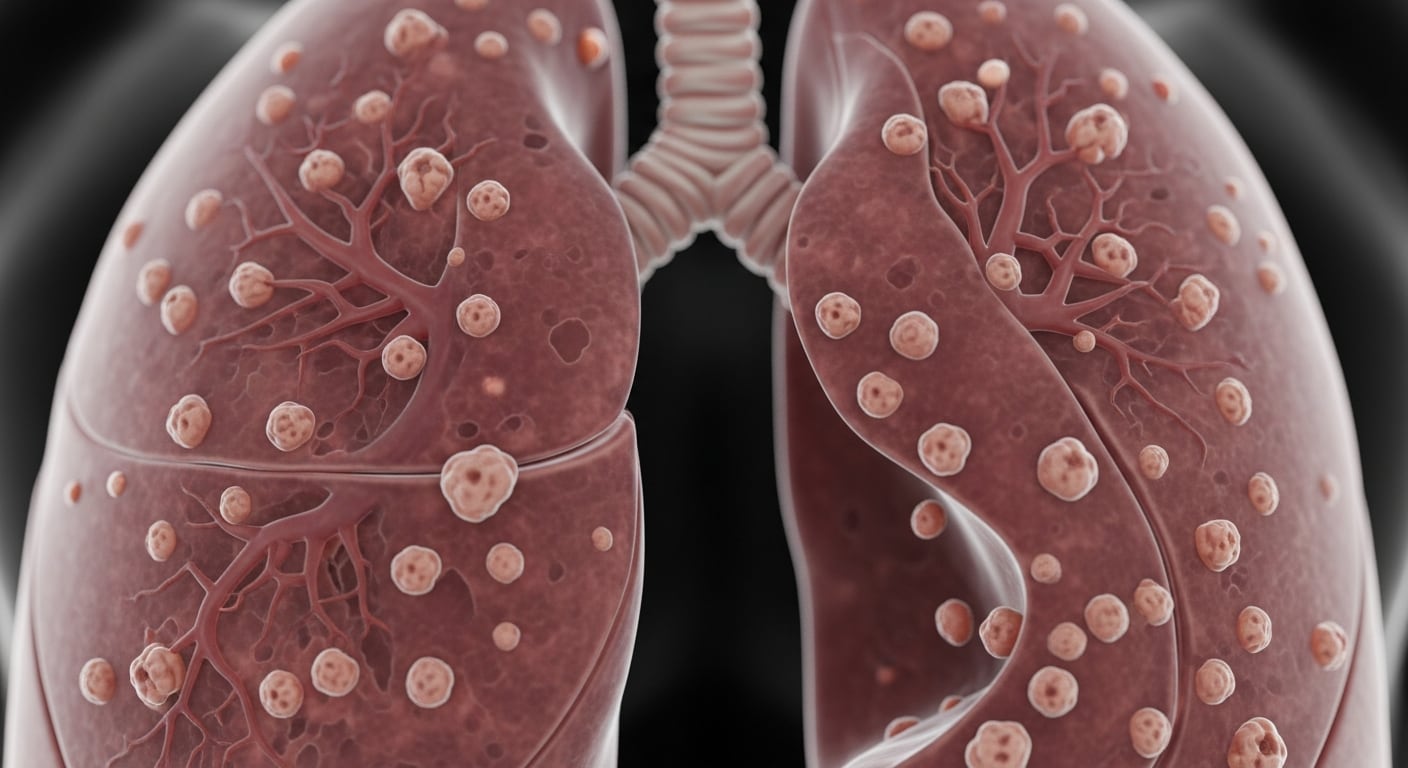

¿Qué son los nódulos pulmonares y cuán frecuentes son?

Los nódulos pulmonares son pequeñas masas que suelen visualizarse en estudios de imagen, como la tomografía de tórax. Estos hallazgos son frecuentes en la población adulta. De acuerdo con Mayo Clinic, al menos la mitad de las personas mayores de 50 años puede presentar uno o más nódulos, aunque la mayoría no implica un peligro considerable para la salud.

Especialistas de Mayo Clinic afirman que entre el 96% y el 98% de los nódulos pulmonares son benignos, incluso en quienes presentan factores de alto riesgo, como el tabaquismo. El Dr. David E. Midthun, neumólogo de la institución, explica: “La gran mayoría de estos nódulos corresponde a tejido cicatricial de infecciones pulmonares previas y suele no causar síntomas”.

La preocupación médica surge cuando se cumplen ciertos criterios clínicos específicos. El equipo médico evalúa el tamaño y la apariencia del nódulo, la edad del paciente, los antecedentes de tabaquismo, la presencia de varios nódulos y si existen antecedentes de cáncer o exposición a asbesto. Además, comparar imágenes previas puede ser clave para analizar la evolución del nódulo. El Dr. Midthun señala: “Estas imágenes suelen ser muy valiosas para determinar si un nódulo es canceroso”.